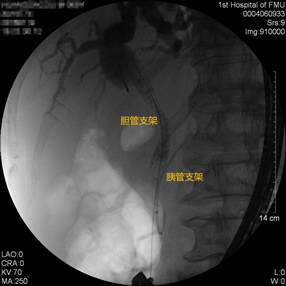

胃毕-Ⅱ术后球囊扩张狭窄胆管 胃毕-Ⅱ术后支架植入 胃毕-Ⅱ术后胆管胰管扩张

胃毕-Ⅱ术后胰管胆管双支架植入 胃毕-Ⅱ术后胆管金属支架植入